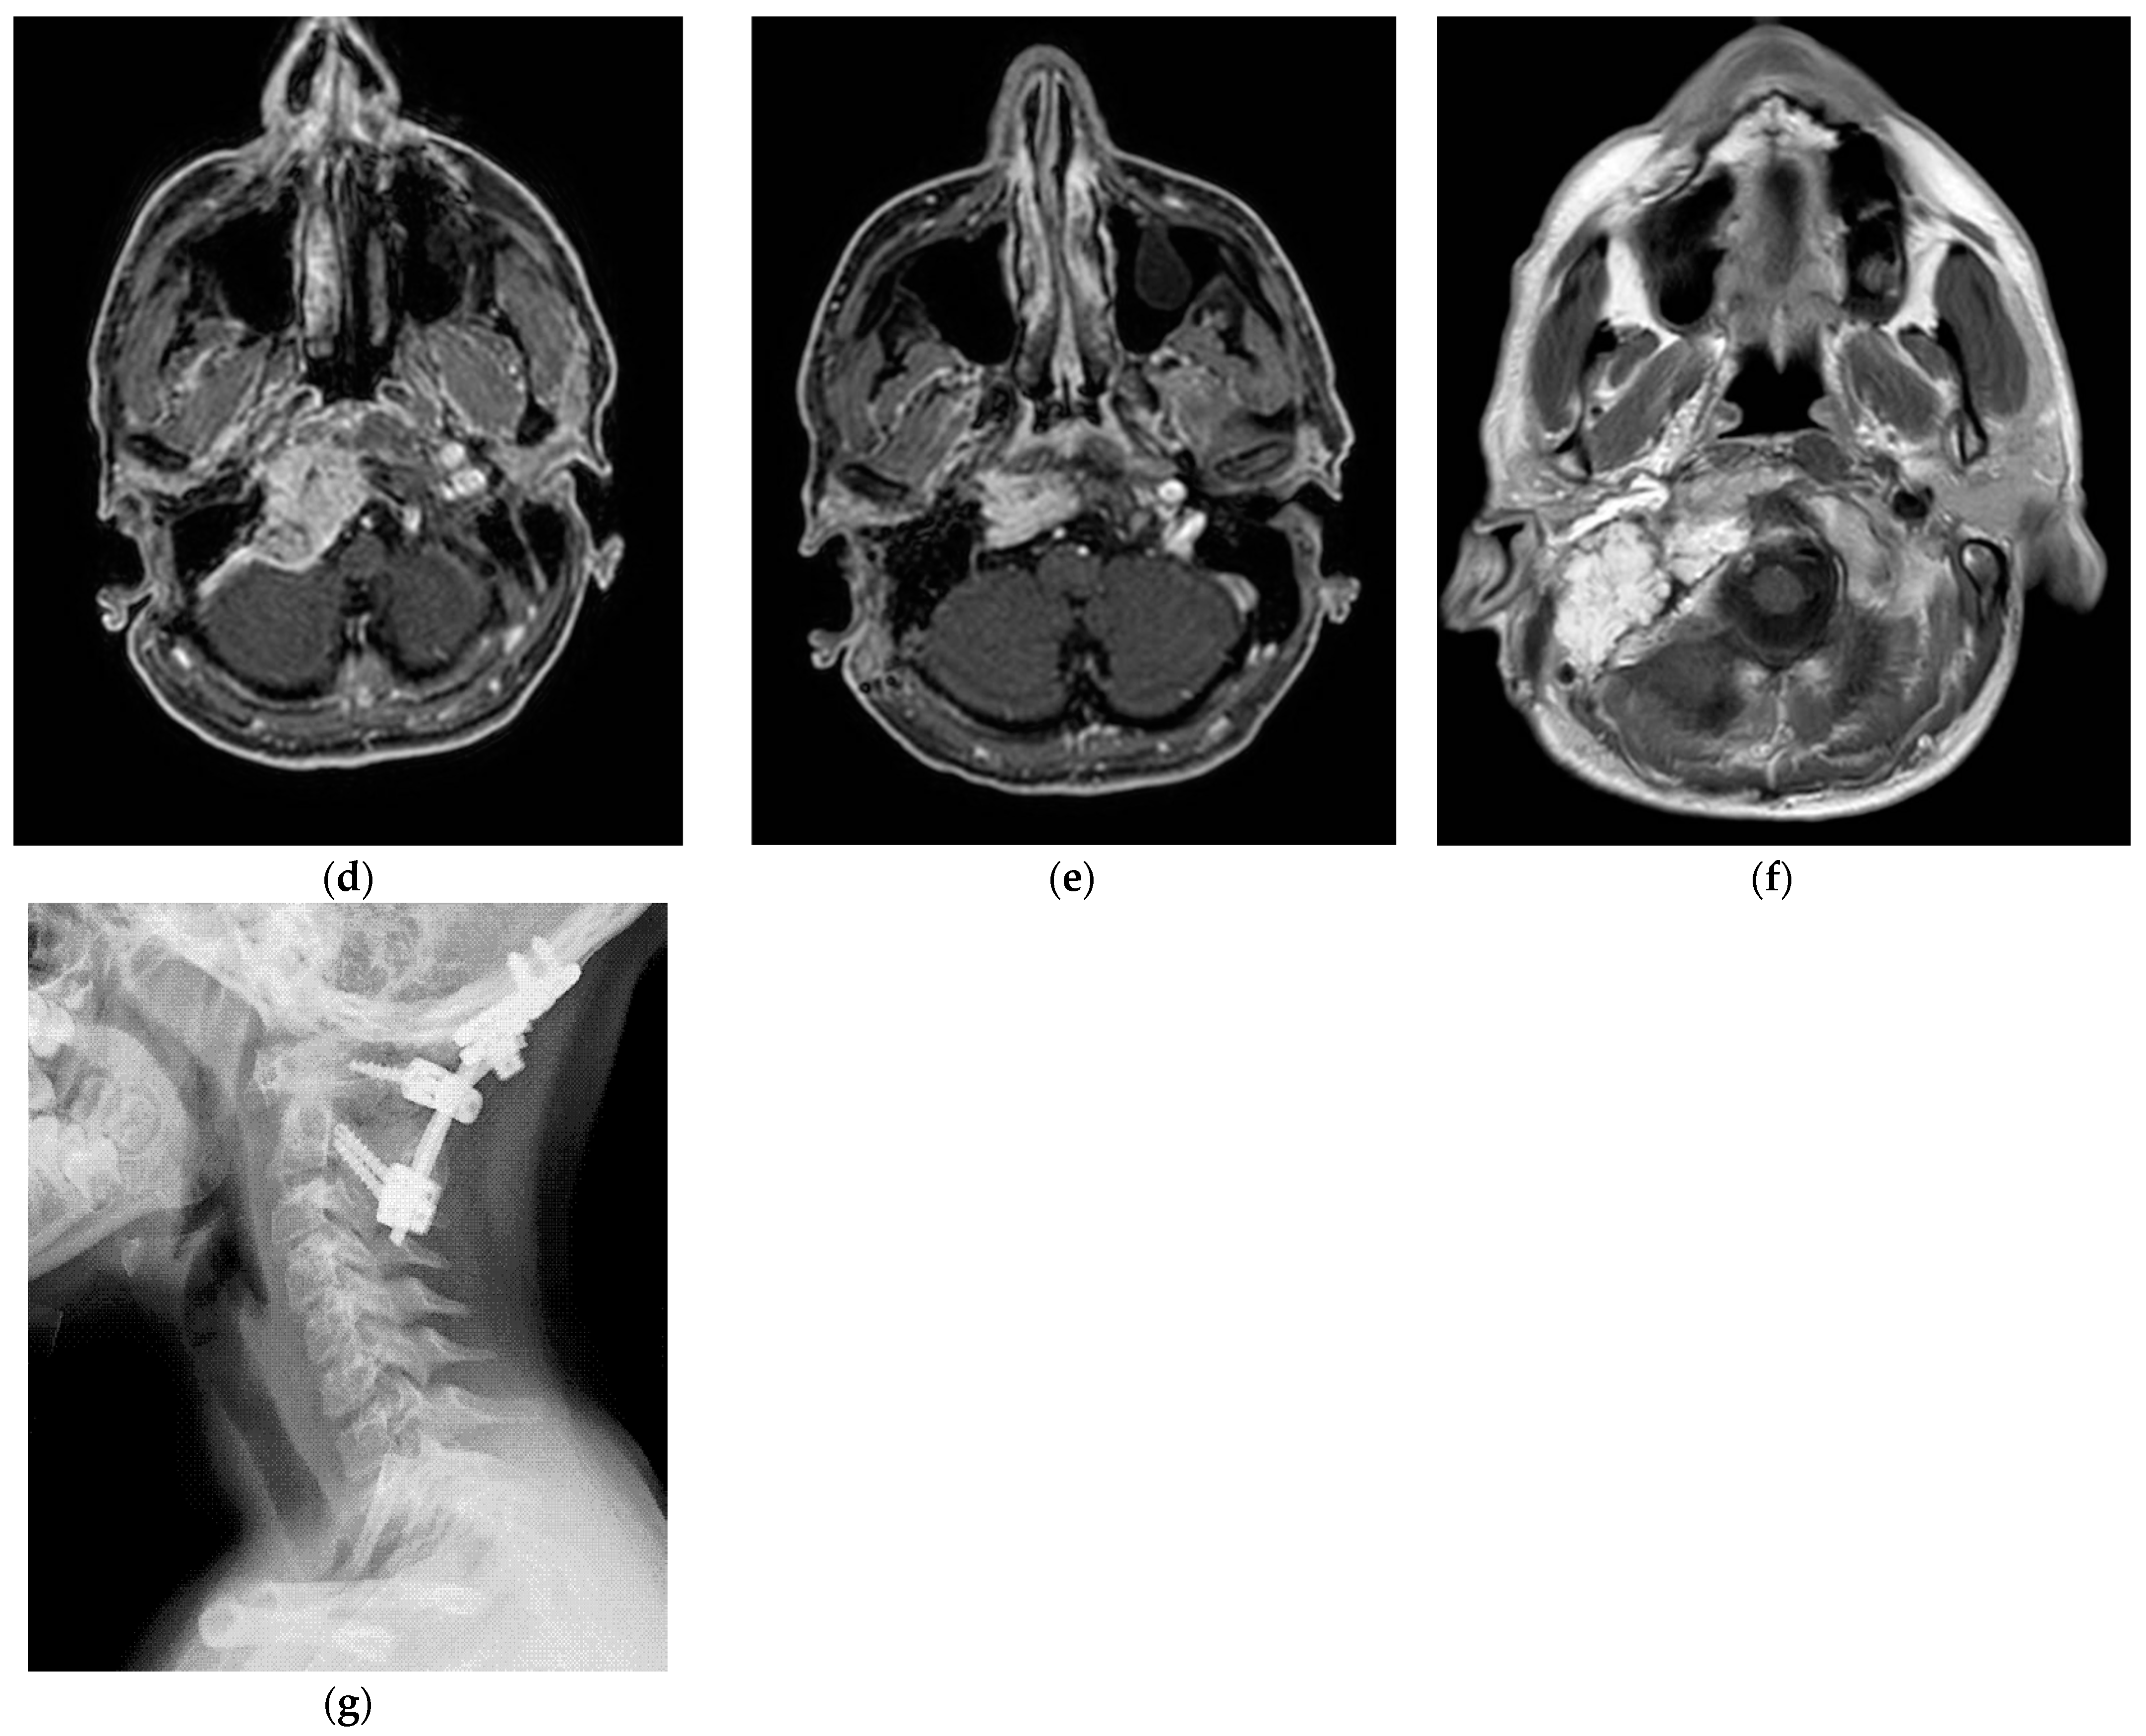

5.1. Case 1: (C4Di2)

5.2. Case 2: (C3Di1 + Stage I VP)

5.3. Case 3: (C4Di2Vi)

5.4. Case 4: (C3Di2 + Stage II Vagal PGL)

5.5. Case 5: (C3Di2Vi)

5.6. Case 6: (C4Di2Vi)